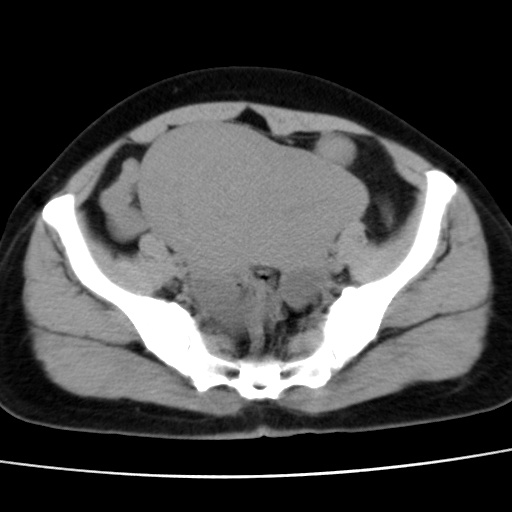

子宫多发肌瘤吗

多发性子宫肌瘤.

考虑多发子宫肌瘤,子宫直肠窝双囊性占位,另直肠周围脂肪密度增高,不知有何病史

支持考虑多发子宫肌瘤~!子宫直肠陷凹积液?

支持考虑多发子宫肌瘤~!子宫直肠陷凹积液!

子宫肌瘤,宫体部后方见液性密度影,是肠道还是子宫与直肠陷窝积液不好说,我觉得它的位置有点高

支持考虑多发子宫肌瘤!子宫直肠陷凹积液!

患者发热,而子宫直肠窝液性灶有明显边缘且局限且囊性,不除外为包裹性积液或脓肿

支持考虑多发子宫肌瘤,子宫直肠陷凹积液可能。

考虑多发子宫肌瘤

1)考虑子宫肌瘤可能性大。2)子宫后方囊性占位性病变,不排除卵巢囊肿可能。

考虑多发子宫肌瘤。子宫后方囊性占位性病变,不排除卵巢囊肿可能。